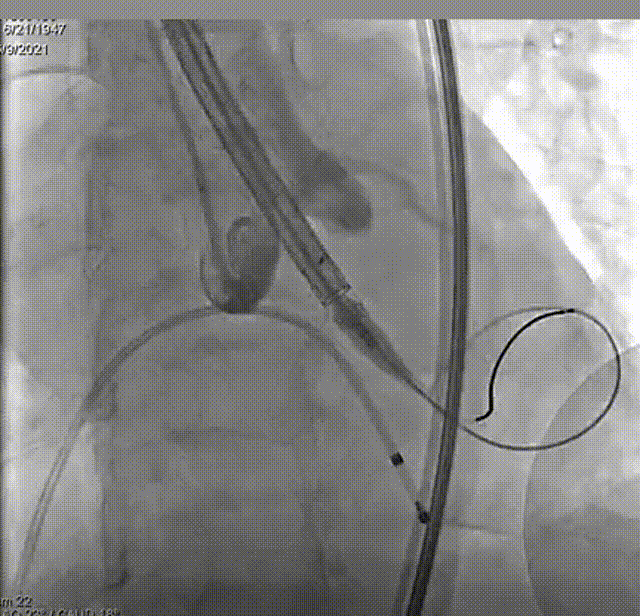

主动脉根部造影,双侧冠脉血流未见明显异常。

选取20mm球囊180bpm频率下快速起搏预扩。球囊扩张后未见反流,左右冠血流未受影响,选择VenusA-Plus 26型号瓣膜植入。

预扩

输送系统输送至窦底,行主动脉根部造影,借助无冠窦猪尾造影定位,由于该患者基础心率较缓慢,瓣膜无起搏顺利释放。

释放